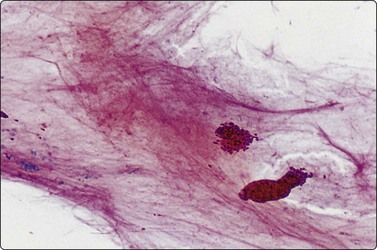

image image

Fig. 7.15 Regenerative epithelial atypia in mastitis

(A) Atypical, reactive/regenerating epithelial cells with a background of histiocytes, inflammatory cells and debris (MGG, HP); (B) Corresponding tissue section (H&E, IP).